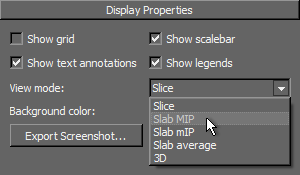

- Choose a View mode— Slab MIP, Slab mIP, or, Slab average — in the Scene's Views Properties panel.

MIP |

mIP |

Average |